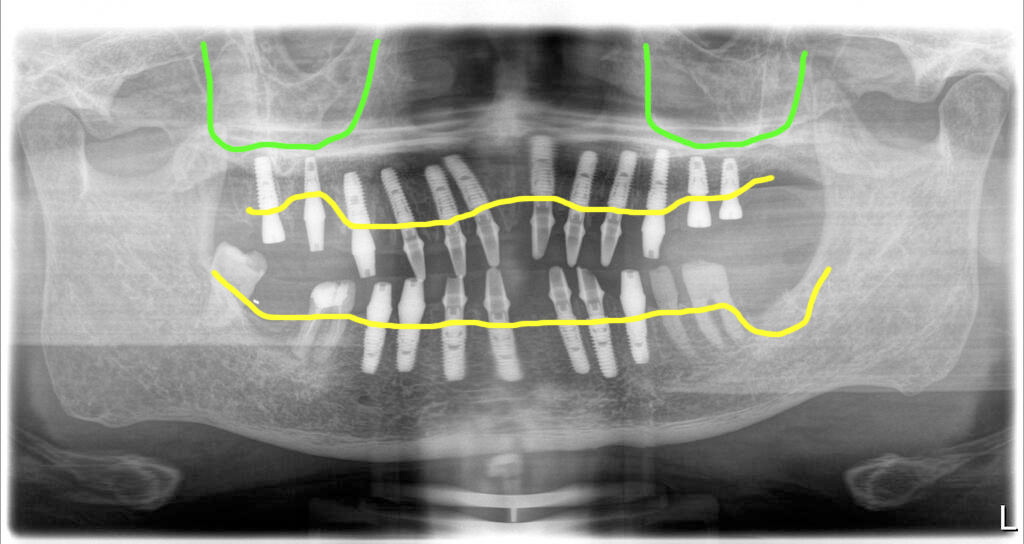

상악은 모두 발치 후 임플란트를 12개 심었고, 좌측 상악동은 측방접근 뼈이식을 하면서 식립을 했습니다. 상악동거상술과 함께 식립된 임플란트는 고정이 부족해서 힐링을 끼워두고 임시치아에 적용하지 않았어요.

그리고 아래는 치아머리가 어느 정도 남아있는 치아는 남기고 나머지의 치아를 발거하고 임플란트를 7개 식립했습니다. 고정이 좋은 임플란트들은 모두 지대주를 연결해서 수술당일 임시치아를 제작해서 끼워드렸어요.

발치와 동시에 임플란트, 뼈이식 모두 한 번에 수술을 끝낸 후 4개월 후 최종보철을 만들기 위한 스캔바디 스캔을 했어요. 그리고 다음날 최종보철을 마무리 해서 세팅했습니다.

아래쪽에 빨강색으로 표시된 부분은 자신의 치아를 살려서 다시 크라운으로 치료한 모습입니다. 그리고 마모로 인해 소실된 고경(위턱과 아래턱과의 높이)도 함께 회복했습니다. 전체 맞춤지대주에 지르코니아로 마무리된 파노라마 엑스레이 사진입니다.